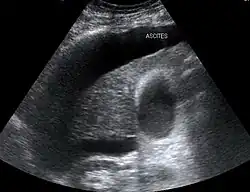

Large volume abdominal ascites

The use of ultrasound has become the standard of care when preparing a patient for paracentesis. Confirmation of an ascitic effusion reduces the risks associated with a dry or blind tap of the abdomen. Anatomic landmarks, such as the midline linea alba approach, were traditionally used as reference points for needle insertion. Phased array or curvilinear ultrasound transducers are typically used in the hospital and outpatient setting to identify ascites in the abdominal cavity. Fluid within the abdominal cavity appears hypoechoic or anechoic (black) on ultrasound. Morison's pouch (hepatorenal recess) is a common starting location in concordance with ultrasound FAST (focused assessment with sonography for trauma) exam. Fluid collection can occur in a number of different locations and may be difficult to find, especially if the patient only exhibits a small volume of ascites. Measurement of the amount of fluid within the abdominal cavity is not necessary or very successful. Identification of sufficient fluid within the abdominal cavity for fluid analysis or to achieve a therapeutic benefit is all that is required to proceed to paracentesis. Ultrasound guidance of the paracentesis can also be used as an additional safety measure to ensure the needle stays within the ascitic fluid and avoidance of important vessels within the abdominal cavity.[5]